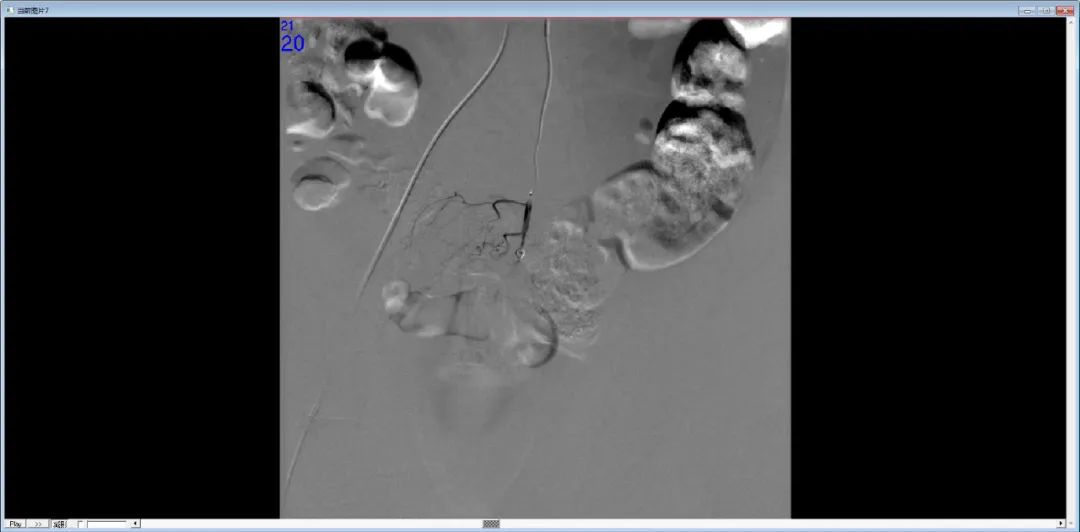

DSA示对比剂外溢